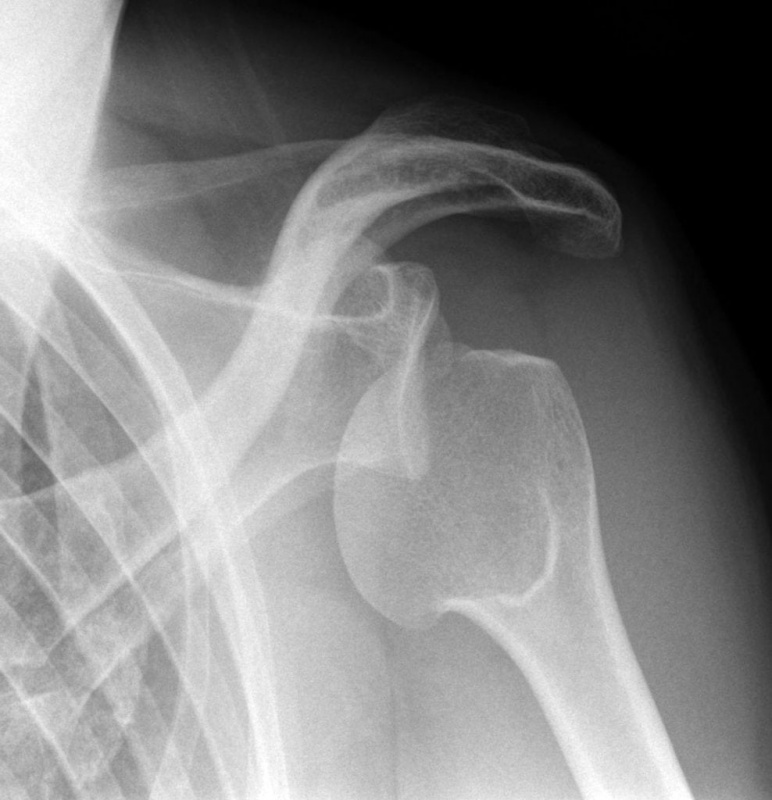

ПІСЛЯ АВТОМОБІЛЬНОЇ АВАРІЇ НА РЕНТГЕНОГРАМІ ВИЯВЛЕНО ПЕРЕЛОМ КІСТКИ В ДІЛЯНЦІ ХІРУРГІЧНОЇ ШИЙКИ. ЯКА КІСТКА МАЄ ТАКУ ШИЙКУ?

варіанти відповідей

РОЗПІЗНАЙТЕ НА РЕНТГЕНОГРАМІ СУГЛОБ, ЩО МАЄ МІЛКУ СУГЛОБОВУ ЗАПАДИНУ І СКРІПЛЕНИЙ ПЕРЕВАЖНО М'ЯЗАМИ, ТОМУ ТУТ ВІДНОСНО ЧАСТО БУВАЮТЬ ВИВИХИ.